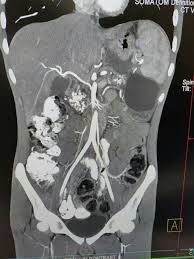

Chronic Calcific Pancreatitis With Pseudocyst Human Anatomy Human Organ Human